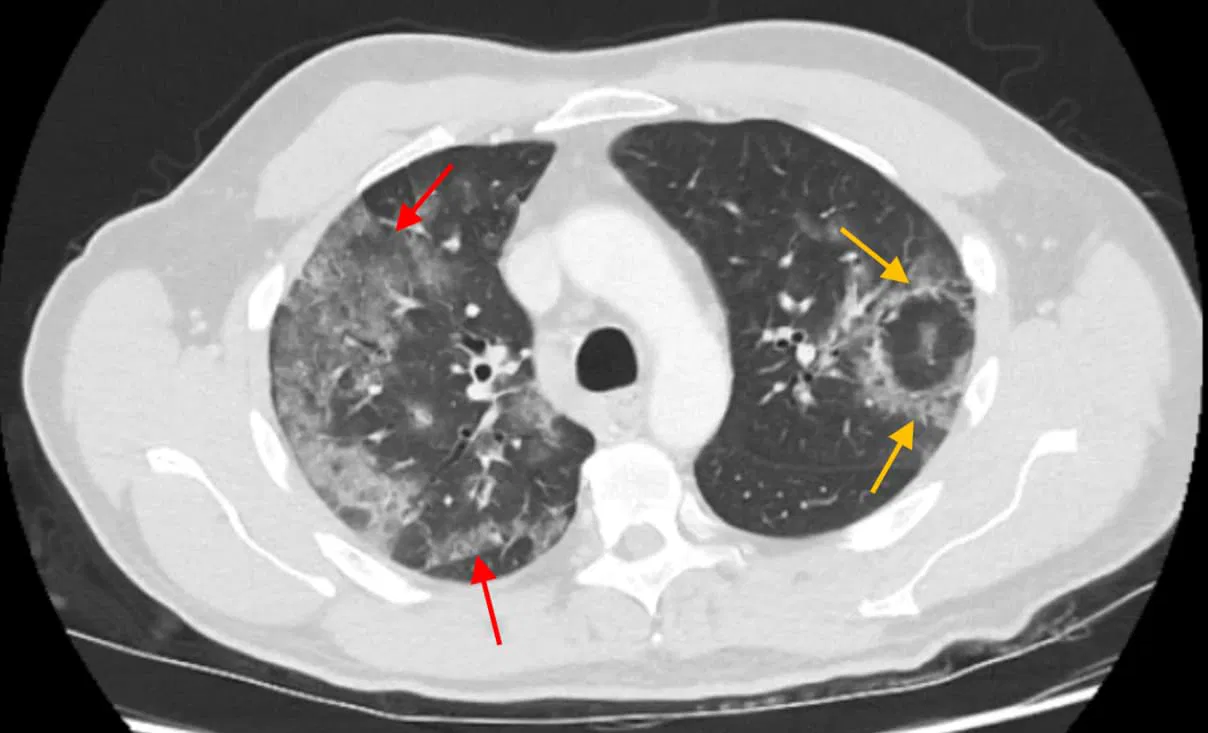

Reversed halo sign is caused by a focal process resulting in central ground-glass opacity surrounded by a more dense ring of consolidation in the lung parenchyma. This CT imaging finding is most characteristically seen in cryptogenic organizing pneumonia (COP) but also occurs in a variety of infectious and noninfectious underlying pathologies, including invasive fungal infections (e.g., pulmonary mucormycosis, aspergillosis), Pneumocystis jirovecii pneumonia, tuberculosis, pulmonary infarction, granulomatous vasculitis (formerly Wegenerโs granulomatosis), lymphomatoid granulomatosis, sarcoidosis, and even in COVID-19 pneumonia. This sign reflects an organizing inflammatory or infectious process with variable involvement of alveolar spaces and interstitium.

The name reversed halo sign refers to the characteristic imaging appearance on CT where a central area of ground-glass opacity is encircled by a denser consolidation, forming a ring-like shape opposite to the classical โhalo sign,โ where a denser nodule is surrounded by ground-glass opacity. Hence, it is a โreversedโ pattern compared to the conventional halo.

The central ground-glass opacity corresponds to alveolar septal inflammation and partial filling of alveolar spaces with inflammatory exudate, maintaining some air content. The surrounding denser consolidation represents more complete alveolar filling with organizing pneumonia (fibroblastic tissue plugging in alveolar ducts and alveoli) or peripheral granulomatous inflammation. The ring of consolidation forms due to peripheral extension of inflammatory cells and fibrosis around the central area, creating the distinctive reversed halo sign pattern.